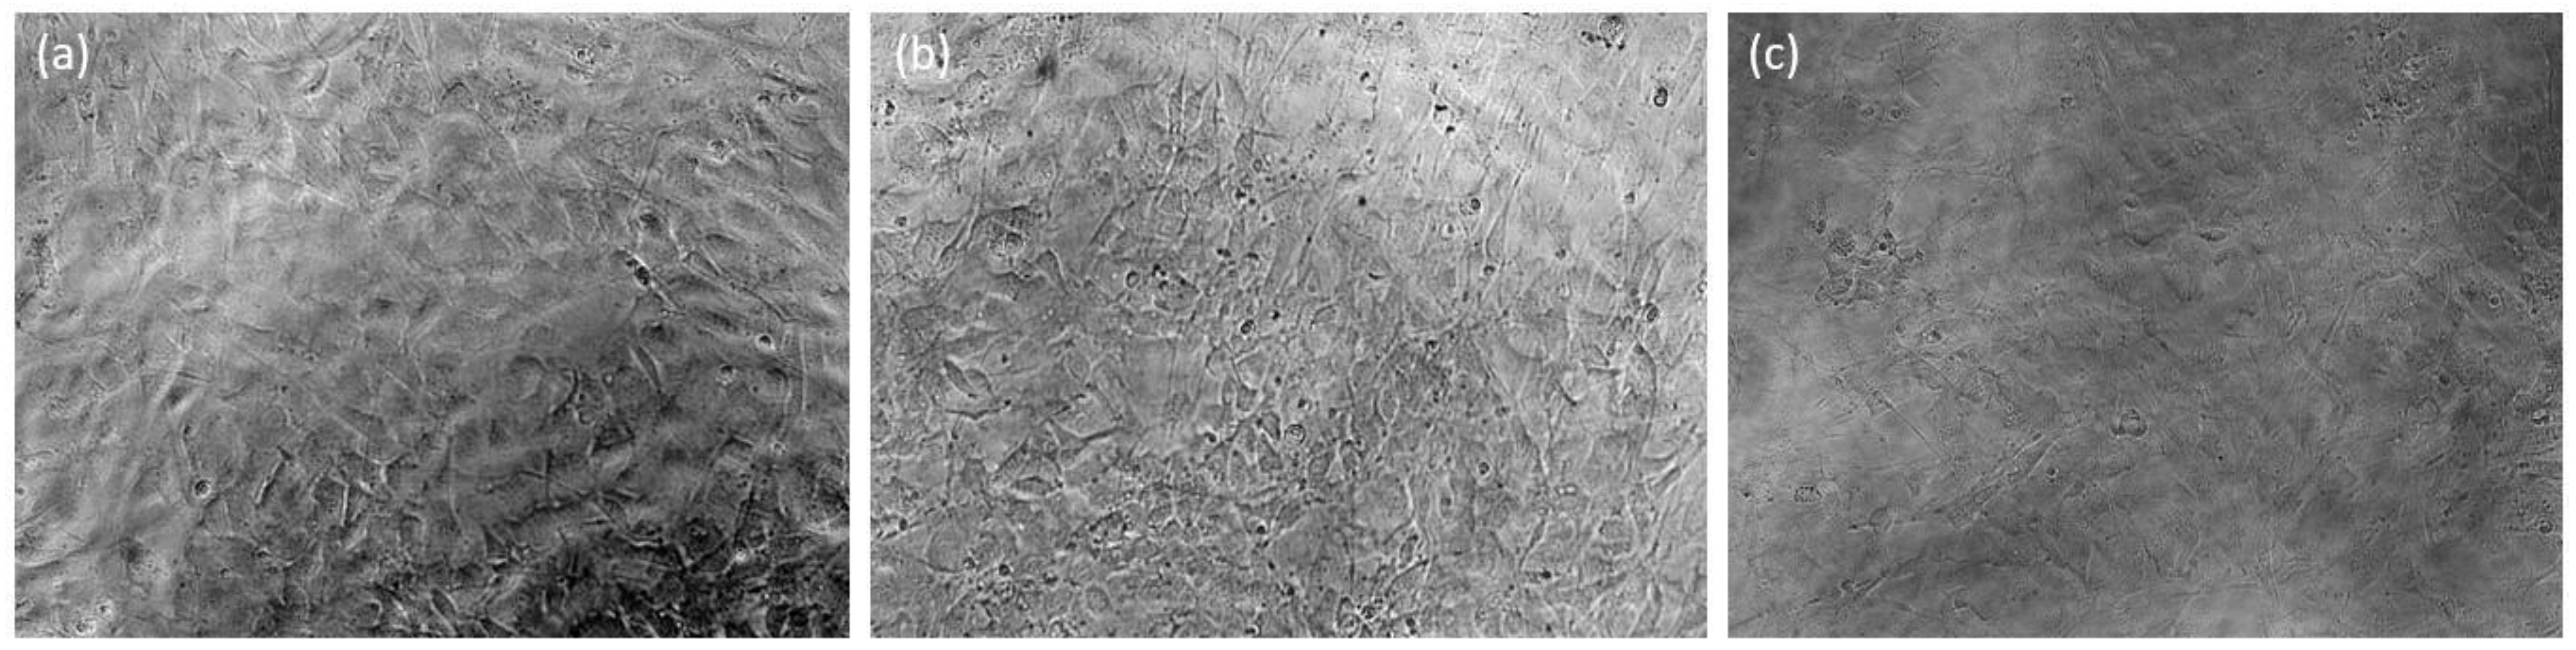

3.3. Cytocompatibility Studies